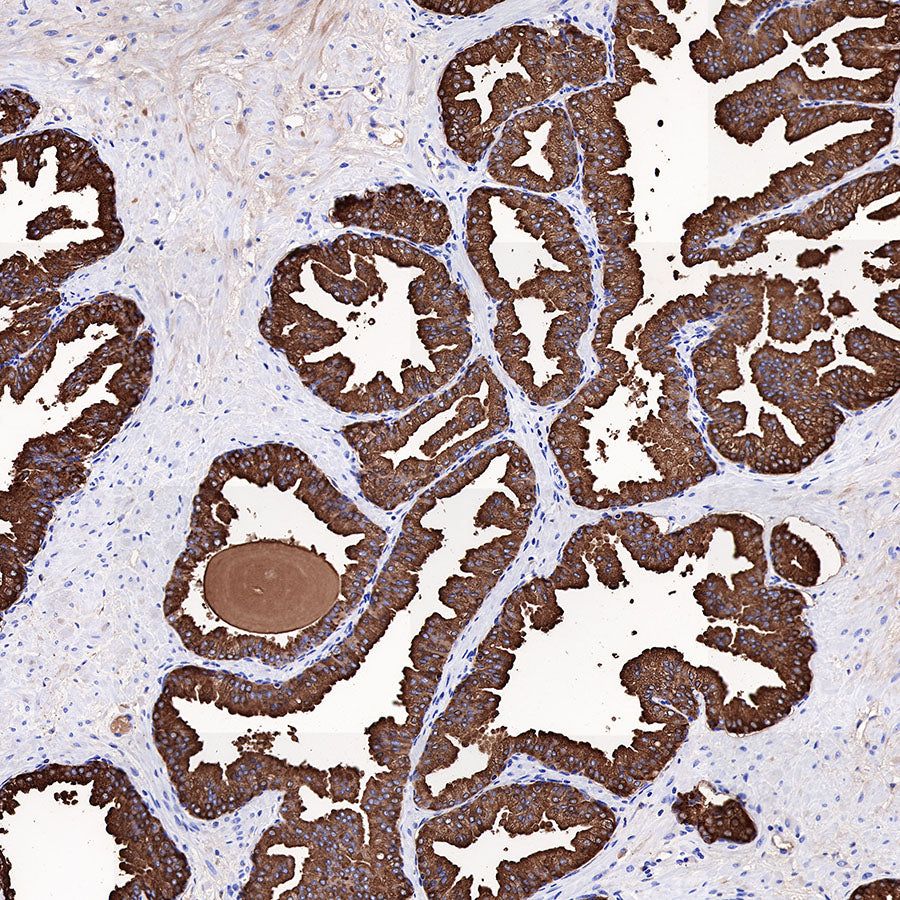

Immunohistochemistry

Negative control: IHC shows negative staining in paraffin-embedded human breast cancer. Anti-PSA antibody was used at 1/1000 dilution, followed by a HRP Polymer for Mouse & Rabbit IgG (ready to use). Counterstained with hematoxylin. Heat mediated antigen retrieval with Tris/EDTA buffer pH9.0 was performed before commencing with IHC staining protocol.